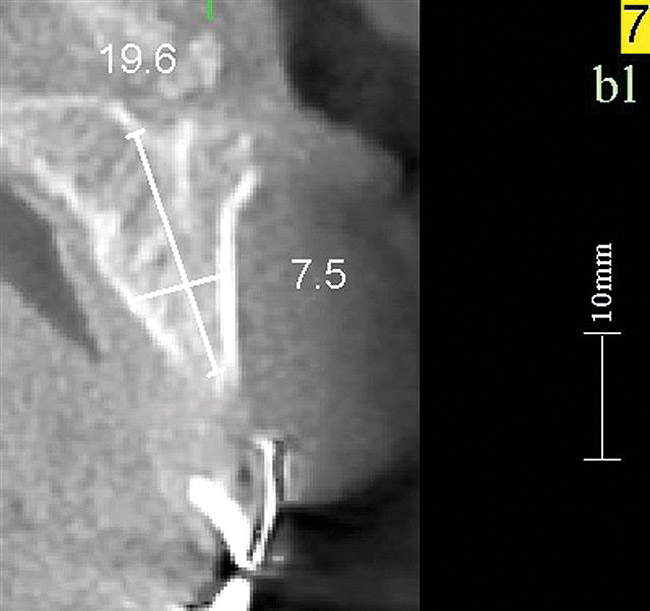

Figure 17   Volumetric characterization of the residual alveolar ridge using CBCT: Fig 17 The coronal section of the maxilla reveals the cortical structure of the alveolar ridge associated with the missing right central incisor at the mid-root level. The buccal plate is identifiable and is characterized by little resorption. Fig 18  The saggital section of the maxillary alveolar ridge is displayed in relationship to the planned contour of the eventual implant crown. Fig 19 Importing DICOM files into planning software permits evaluation of the implant, abutment, and crown relationships with existing bone. These images readily characterize both the possible 6-mm mesiodistal width and the possible displacement of the implant 3-mm apical and 2-mm palatal to the planned gingival zenith.

Figure 18    Volumetric characterization of the residual alveolar ridge using CBCT: Fig 17 The coronal section of the maxilla reveals the cortical structure of the alveolar ridge associated with the missing right central incisor at the mid-root level. The buccal plate is identifiable and is characterized by little resorption. Fig 18  The saggital section of the maxillary alveolar ridge is displayed in relationship to the planned contour of the eventual implant crown. Fig 19 Importing DICOM files into planning software permits evaluation of the implant, abutment, and crown relationships with existing bone. These images readily characterize both the possible 6-mm mesiodistal width and the possible displacement of the implant 3-mm apical and 2-mm palatal to the planned gingival zenith.

Figure 18

Figure 19    Volumetric characterization of the residual alveolar ridge using CBCT: Fig 17 The coronal section of the maxilla reveals the cortical structure of the alveolar ridge associated with the missing right central incisor at the mid-root level. The buccal plate is identifiable and is characterized by little resorption. Fig 18  The saggital section of the maxillary alveolar ridge is displayed in relationship to the planned contour of the eventual implant crown. Fig 19 Importing DICOM files into planning software permits evaluation of the implant, abutment, and crown relationships with existing bone. These images readily characterize both the possible 6-mm mesiodistal width and the possible displacement of the implant 3-mm apical and 2-mm palatal to the planned gingival zenith.

Figure 19

Volumetric imaging offers several advantages, including the 3-dimensional (3-D) assessment of the residual alveolar ridge, as well as sufficient resolution of the adjacent teeth to assess bone levels and periapical lesions. CBCT imaging offers access to volumetric imaging with the advantage over medical CT imaging of reduced radiation dose.10 A CBCT image permits the careful measurement of mesiodistal osseous dimension, buccolingual osseous dimension, and occlusogingival dimension of the alveolus, as well as the edentulous space (Figure 17 through Figure 19). The Rules of Six are readily interpreted from CBCT images. Using the Rules of Six, however, does not require that a CBCT image be produced.

Imaging of the proposed crown contour in the volumetric image permits the linear measurement of the located zenith to the bone crest in three dimensions (Figure 18). Thus, the desired 3-mm apical displacement and 2-mm palatal displacement of the implant/abutment interface can be evaluated. This rule serves as both a therapeutic guide—determining where the implant should be placed—as well as a diagnostic guide—determining whether there is enough bone to permit ideal implant placement. When viewing the linear relationship of the existing bone crest to the gingival zenith, the presence or absence of bone at this location offers direction in clinical decision-making. If ideal esthetics is desired and insufficient bone volume is observed, then the decision to perform bone augmentation can be made. If there is excess bone, the decision to place the implant in a subcrestal position can and should be made.